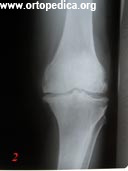

2. Больной Д. рентгенограмма левого коленного сустава в прямой проекции до операции. Диагноз - артроз коленного сустава 3 ст.